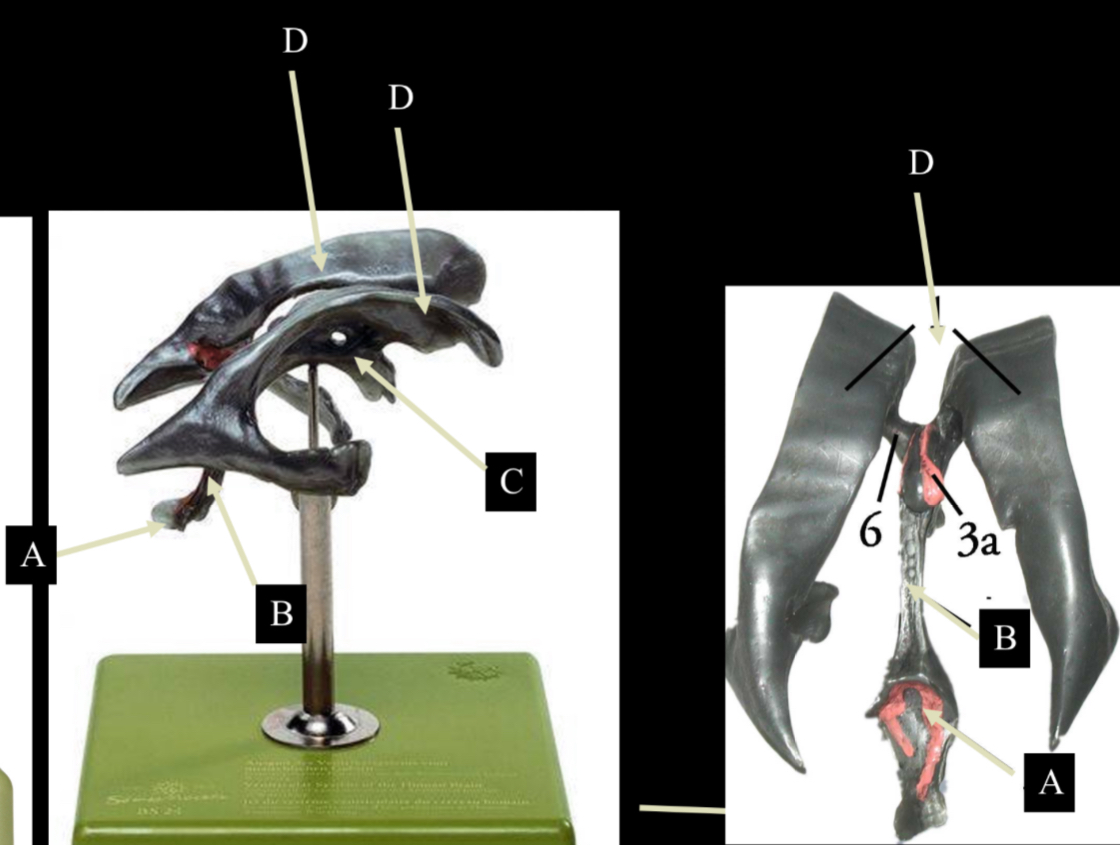

What is D?

lateral ventricle

Imagine thin membrane separating the 2 lateral ventricles

septum pellucidum

What is C?

3rd ventricle

What is B?

cerebral aqueduct

What is A?

4th ventricle

What is below A at the very end?

central canal (spinal cord)